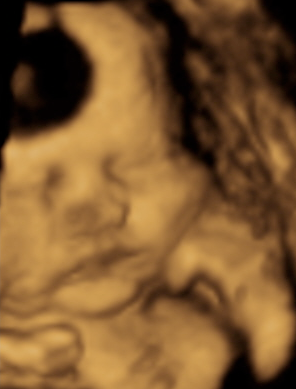

This past Sunday we had our ninth ultrasound. Yes, I said ninth. Most people usually only get three or so, but we’ve had nine (so far)! Our first ultrasound was when I was about five weeks pregnant because I had a “threatened miscarriage” – scariest ultrasound of them all/scariest day of my life. At the time, our baby looked like a little pea. Then, a week later we had a follow up ultrasound with my doctor so she could see what the ER saw the week before (baby began to look like a tadpole this time). My doctor then sent us to a specialist for follow up work and I had my third ultrasound at ten weeks and our baby finally looked like a little human. Then, we decided that we wanted to know the sex of our little one so we bought the “Full House” package at 4D baby; which meant two ultrasounds. Our fourth ultrasound was at fifteen weeks and this is when 4D baby told us we were going to have a girl! Then, we went to our last visit with the specialist at eighteen weeks for our fifth ultrasound and the specialist confirmed that we were indeed having a girl. We decided to use our second visit (sixth ultrasound) with 4D baby at twenty-four weeks so we could take the video with us on our trip to Ohio to share it with our family, but that didn’t go as planned… baby girl was breech and had the umbilical cord in front of her face. So we got a re-do in two weeks. The re-do (seventh ultrasound) didn’t work either – she was head down and had her hands in front of her face the whole time. So we got another re-do (eighth ultrasound) with the owner, but she didn’t cooperate for her either. Despite me drinking tons of apple juice beforehand baby girl slept the whole time and had her hands in front of her face AGAIN! So what now? We got a fourth re-do – our ninth ultrasound! We weren’t complaining about all these re-dos because they were free! Our fourth re-do (ninth ultrasound), went a little better and we actually got to see some of her face. So here’s what we got to see:

Then she finally gave us a glimpse!...

and my favorite - her smile: